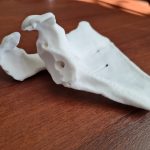

Наталия Нестерова обратилась за консультацией в Новосибирский НИИТО им. Я.Л. Цивьяна. Врач травматолог-ортопед, к.м.н. Сергей Чорний предложил пациентке альтернативный вариант — установку 3D-импланта, созданного специально для неё.

«Судя по объёму дефекта, сустав разрушался на протяжении многих лет. Почему этот процесс вообще начался? Это особенность заболевания — ревматоидного артрита. В результате утрачивается не только суставной хрящ, но и костная ткань. У этой пациентки, в частности, была в значительной степени утрачена костная ткань лопатки, и в результате установить ей стандартный эндопротез было технически невозможно. Единственная возможность помочь пациентке была только в изготовлении индивидуального импланта», — объясняет хирург.

Наталия Автономовна стала первой пациенткой института, которой предложили индивидуальный имплантат плечевого сустава. Однако технология изготовления таких протезов широко применяется в отделении эндопротезирования и эндоскопической хирургии суставов (тазобедренный, коленный суставы) и в нейрохирургическом отделении, и принцип создания имплантата был аналогичный. Хирурги совместно с инженерами разработали модель на основе результатов компьютерной томографии — с учётом всех нюансов анатомии пациентки. Полученный имплантат из титанового сплава стерилизовали и подготовили к хирургическому вмешательству.

«Мы с техниками длительное время согласовывали форму имплантата, его положение, направление — это заняло порядка 4 месяцев. Операция прошла успешно, трудностей не возникло благодаря тщательной подготовке. Пациентка выписывается уже через неделю после операции», — отмечает Сергей Иванович.